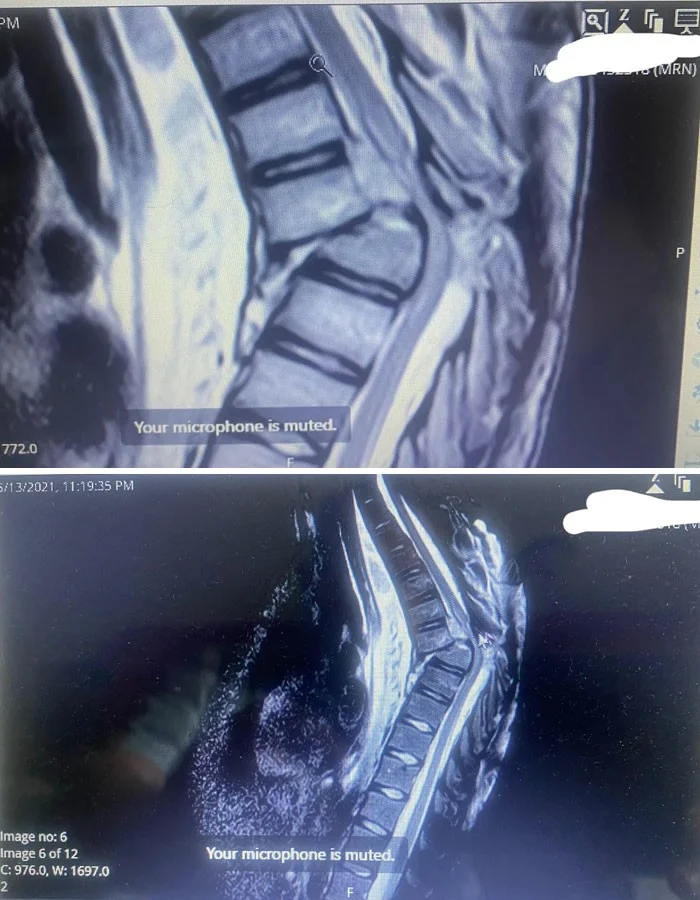

16. «Мой рентгеновский снимок после перелома спины»

25. «Папа сказал, что у него побаливает спина»